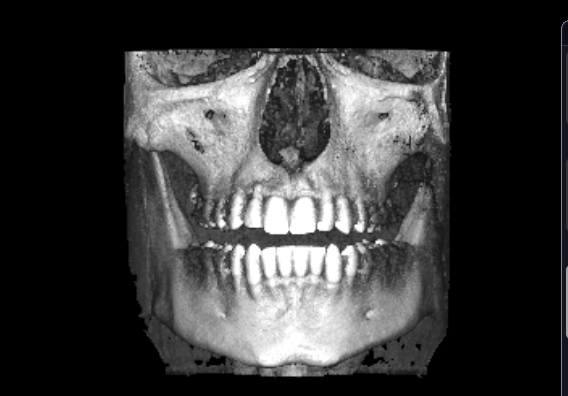

if you could recommend me surgeon in Russia, I'd be very grateful. I found 2 good ones andreishchev who is responsive and Kurakin who ignored me on instagram but i joined their telegram channel